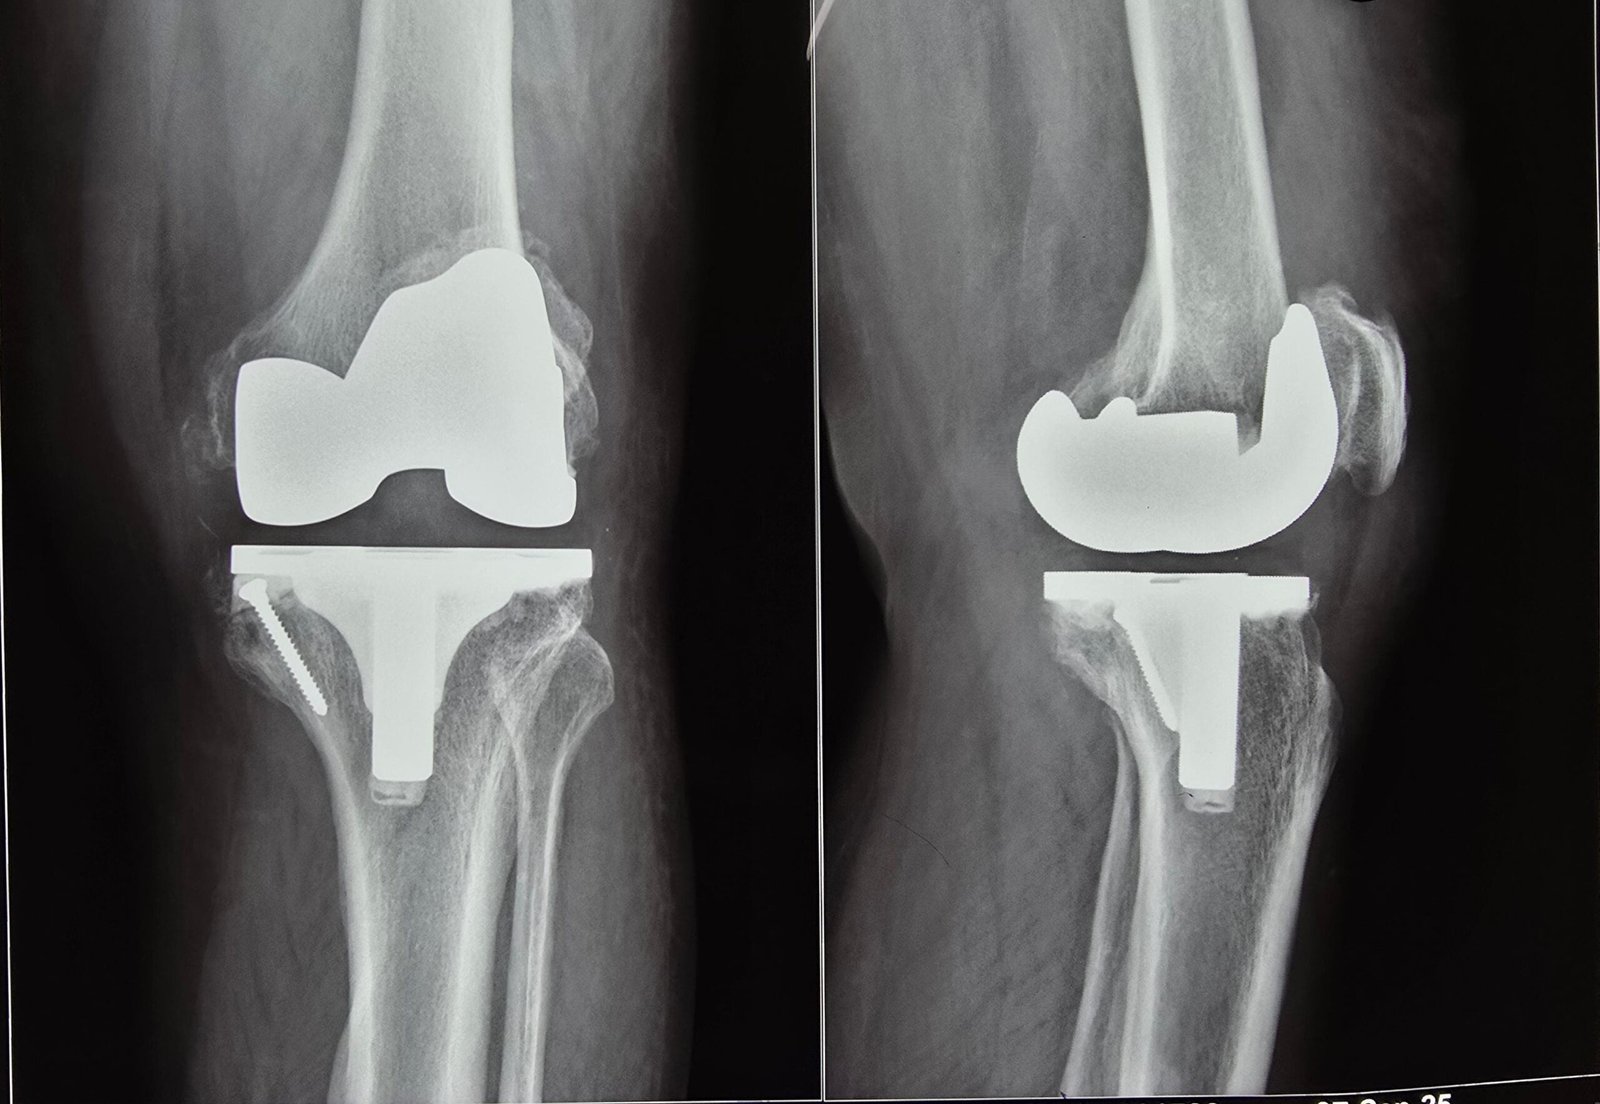

Post-Op X-Ray